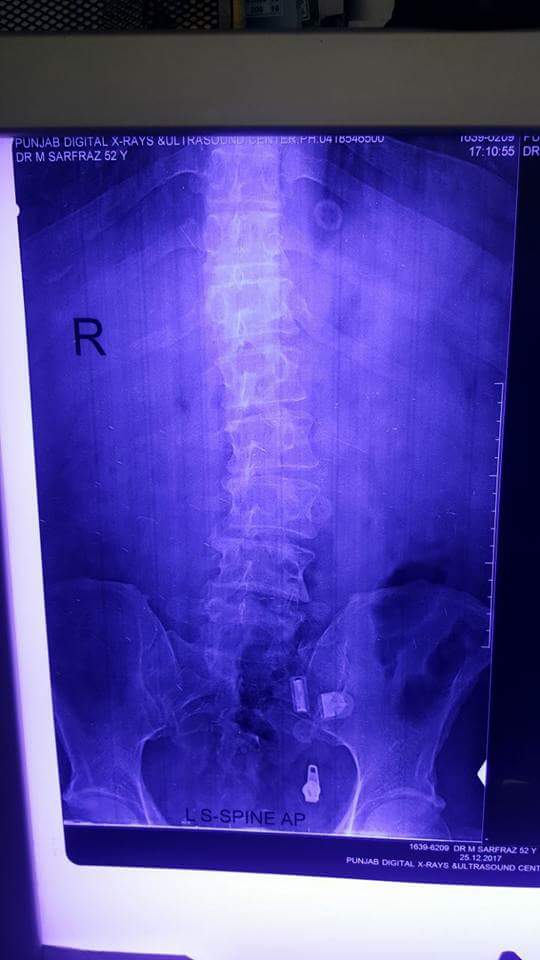

Asking for Self, Male, 52 years old, Faisal abad. PAKISTAN

Lower back pain couple of years. Pain right thigh right knee joint. No recent trauma.

Thank you Dr sarfraz for asking. Although the radiographs and MRI are showing degenerative changes of spine and disc bulge as well, but a clinical examination is required. Cauda equina syndrome, characterized by loss of bladder or bowel function and saddle Anesthesia warrants emergency surgery. All other procedures are elective, depending on the clinical significant finding.

X-ray's shows it's structural or postural, need examination.

mri shows L3/4 disc prolapse.

if symptoms are worse, see a doctor